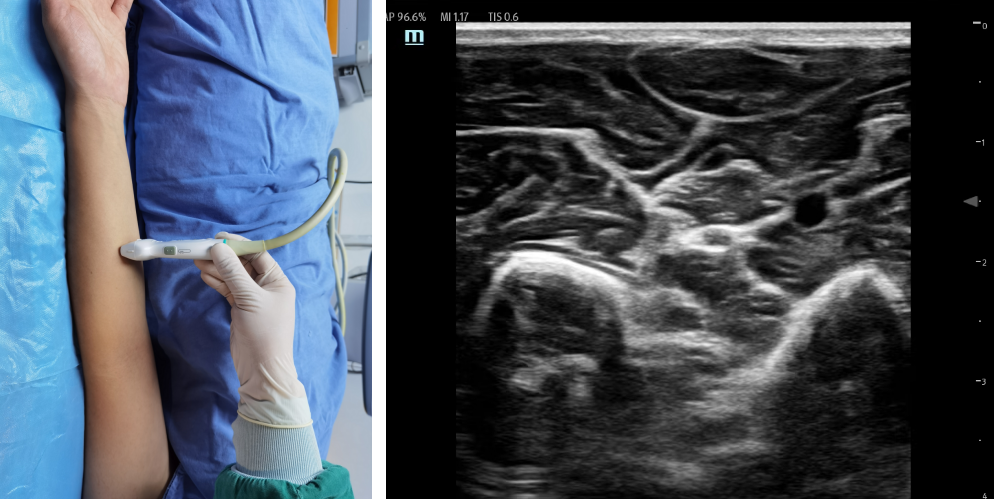

②前臂入路:体位:平卧位,肘关节伸直,掌心向上。关键点是在肘关节以上找到正中神经,然后往下追踪。在前臂先大体鉴定出指深屈肌和指浅屈肌,正中神经就位于两者之间。或者找出桡骨和尺骨,在这两个骨的中间上方高回声的结构,一般为正中神经。平面内法,从外侧和内侧进针均可。药物用量:0.25%-0.5%罗哌卡因3-5ml。